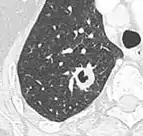

• If there is a central cavity, then a thin wall points to a benign cause whereas a thick wall is associated with malignancy (especially 4 mm or less versus 16 mm or more).[10]